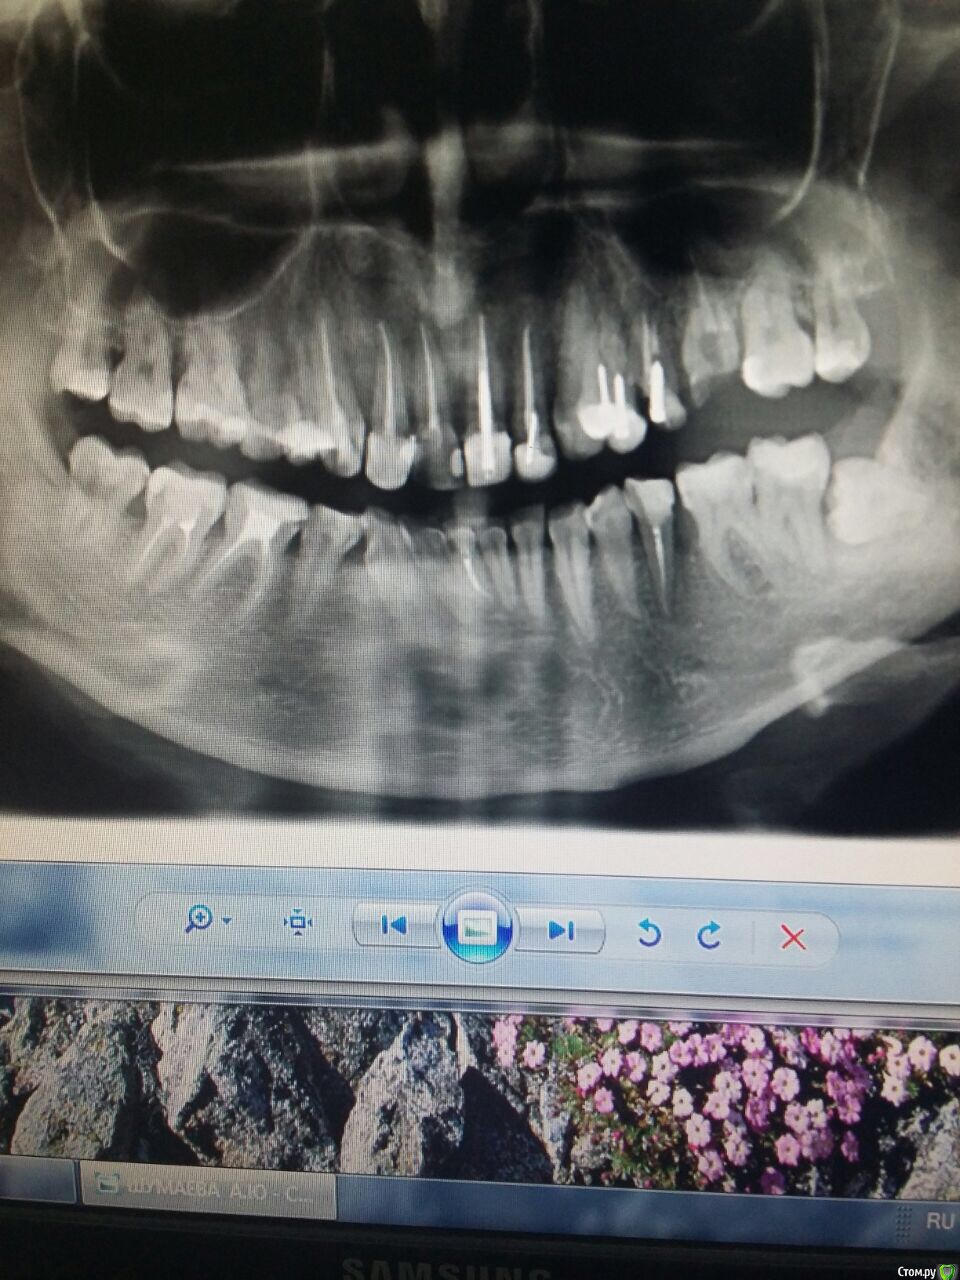

Алена87 Опубликовано 19 декабря, 2017 Поделиться Опубликовано 19 декабря, 2017 Здравствуйте. Воспалились дёсны, пошла к порадонтологу с панорамным снимком. Мне почистили зубы ультразвуком (Безон вроде назывался аппарат)воспаление сняли , но над верхними передними 2-ми все равно ещё присутствует отечностьПародонтолог считает возможным сделать Вектор и то не настаиваетХотя при этом ставит паподонтит средней тяжести Пошла на кослультацию к другому пародонтологу, где сразу было предложено сделать закрытый кюретажХотелось бы узнать , что предпочтительнее в моем случаи ? Вектором только можно обойтись? Ссылка на комментарий

Алена87 Опубликовано 19 декабря, 2017 Автор Поделиться Опубликовано 19 декабря, 2017 Вам впринципе нужно заниматься полостью рта. А впроцессе и проблемы этои уйдут. Протезирование, хирургия....Спасибо за откликвопрос все же был в другомПеред имплантацией и постановки коронок, нужно пролечиться Какой из способов (вектор или закрытый кюретаж) в моем случаи предпочтительнее ? Ссылка на комментарий

dok1 Опубликовано 20 декабря, 2017 Поделиться Опубликовано 20 декабря, 2017 Вы уберёте старые коронки и пломбы. Попутно камни и остатки цемента под десной со стенок корней. И, возможно, проблема снимется. Кюретаж - следующий этап. Там, где показан кюретаж, вектор неособо поможет. Ссылка на комментарий